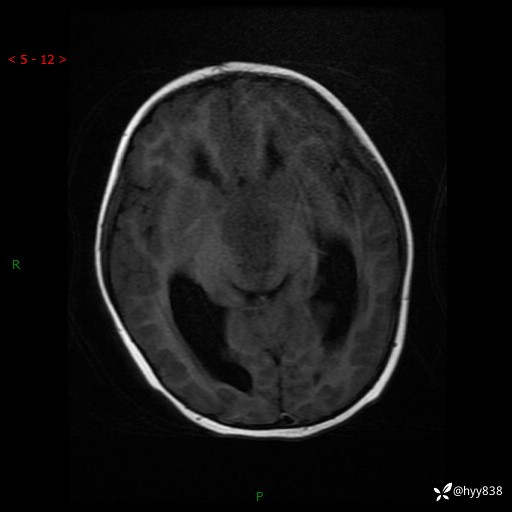

颅脑CT平扫

颅脑MRI平扫+增强

三脑室、四脑室多发病变,如何分析?

髓母细胞瘤 (13)